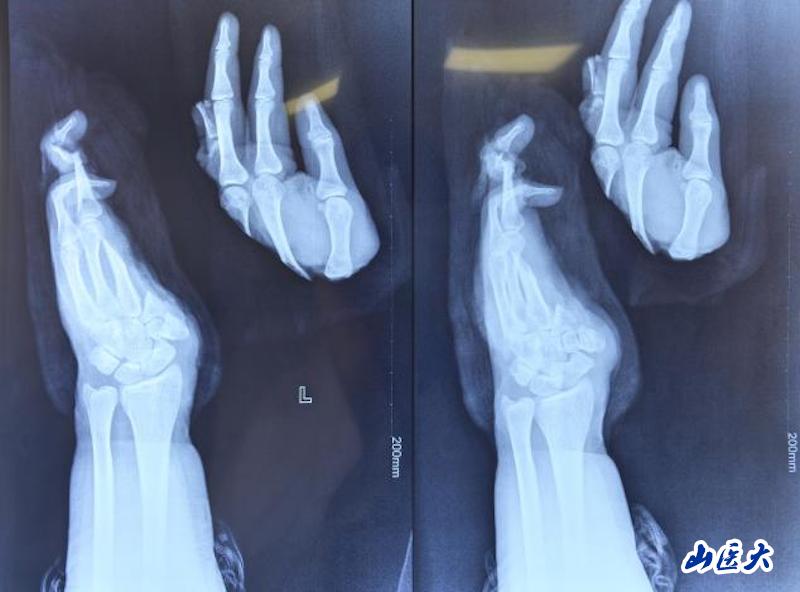

患者小张(化名)是一名在校大学生,为减轻家庭负担,利用课余时间勤工俭学。然而,一次机器操作不慎,导致他的左手掌完全离断。当患者抵达时,离断的手掌被一同送来。我校附属第二医院西院区迅速启动绿色通道,骨手显微组当日值班的李广荣、武永辉、房格三位医师第一时间赶到,患者左手掌中部完全离断,创面污染严重,血管、神经、肌腱等关键结构损伤复杂。医师们马上就位并立即准备再植手术。

手掌血管直径仅0.3-0.5毫米,不足普通针孔大小;医生需要在手术显微镜下,使用比头发丝更细的11-0缝线,将断裂的血管重新吻合。手掌包含27块骨骼、多条肌腱、复杂的神经血管网络;再植手术必须依次完成骨骼固定、伸屈肌腱修复、神经对接、动脉静脉吻合等多个环节,每个环节都要求极高的精度和恰当的顺序安排。

无影灯下,李广荣、武永辉、房格等医师全神贯注。首先彻底清创,标记重要的神经和血管;接着固定掌骨,建立稳定的骨架;然后开始最关键的环节——血管吻合。然后是神经吻合,这关系到手掌未来的感觉和功能恢复。最后是肌腱缝合,为手部运动功能打下基础。6个小时,在高度集中和精细操作中转瞬即逝。当最后一针缝合完成,小张离断的手掌重新回到了他的腕部,血运良好。